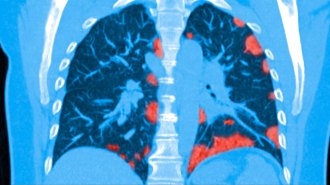

Health & MedicineSome patients who survive COVID-19 may suffer lasting lung damage

Results from a study in China suggest that some COVID-19 patients will be left with long-term lung problems.